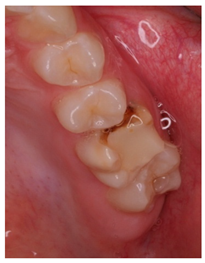

The question from scenario 1a was open-ended; participants were asked to provide a diagnosis of a lesion in tooth 3.6. A total of 41.5% of the surveyed students considered that the image presented a retentive pit/fissure or stained pit/fissure; 39% of them answered that the image exhibited a carious lesion. The answers “healthy”, “early carious lesion”, and “chronic carious lesion” were less frequent: 2.4%, 9.8%, and 7.3%, respectively. For this question, the correct answers were: “retentive pit/fissure or stained pit/fissure” and “chronic carious lesion”. “Healthy” and “carious lesion” were considered as incorrect. Thereby, 48.8% of the surveyed students answered correctly (Figure 1).

For scenario 1b, students were required to order different complementary diagnostic tests from more to less adequate for the diagnosis of the presented case. The most prevalent answer, “bitewing X-ray” (51.2%), “periapical X-ray” (12.2%), and “no complementary diagnostic test is required” (36.6%). The latter was the option considered as correct (Figure 1).

In a similar manner, the surveyed students were asked to order different therapeutic options in scenario 1c. The option “oral health instructions and 6-month follow-up visit” was selected by 51.2% of the participants. This answer was considered as correct Additionally, 9.8% of the students would perform a “pit and fissure sealing”, 7.3% would opt for a “2-year follow-up visit”, and 2–4% would carry out a resin-based obturation/filling (Figure 1).

The results from the present study confirmed that approximately half of the last-year students from the degree in dentistry proposed a correct diagnosis for the first clinical scenario, following the criteria established by The International Caries Consensus Collaboration or ICCC [33], in which the extension and activity of the lesion are considered. The question was open-ended, and a high percentage of participants answered “caries”, without providing more details regarding the activity of the lesion.

As advised by the ICCC, the diagnosis of caries, nowadays, has to be based on the visual clinical exploration and the evaluation of individual risk of caries development [34]. Diagnostic tests will act as supporting material for the determination of the extension of the lesion and to control its progression over time. The majority of students selected, as a complementary test, performing a bitewing X-ray to confirm de diagnosis. This could be considered as an indication for “overdiagnosis”, as this test, in the case of an inactive carious lesion limited to the superficial enamel on the occlusal surface, does not provide any additional help to the diagnosis [13]. This tendency to use complementary tests could be explained by the clinical inexperience of the students and by the excessive trend to support diagnosis on complementary tests (Figure 1).

Currently, there is a great tendency towards the restoration of lesions limited to the enamel, although the scientific evidence supports other non-invasive alternatives for the control of these lesions [35]. According to these criteria, an inactive carious lesion categorized as ICDAS II (clinical scenario 1c) should not receive any restorative treatment, but only require oral health instructions and control of individual risk factors, together with follow-up control visits [35]. Interestingly, the percentage of students who correctly answered the therapeutic approach in scenario 1c (51.2%) was higher than those who correctly answered the diagnosis in scenario 1a (48.8%). This difference may have been due to the fact that students who misdiagnosed scenario 1a as “healthy” or “early carious lesion” may have selected “oral health instructions and 6-month follow-up visit” as a therapeutic approach. However, a little more than half of the students selected this non-invasive therapeutic alternative. It should be highlighted that up to 41.7% of the students would place a resin composite restoration, which in this case is considered as an “overtreatment”. Available systematic reviews among the literature regarding the treatment for early carious lesions found a significative proportion of dentists who would propose restorative treatments upon carious lesions for which minimally invasive technique are indicated [30,32]. Thus, it is necessary to orient dental students into a less invasive approach, taking into account the natural progression of the disease, and treating lesions according to their extension and carioactivity. Because the influence of the type of undergraduate formation influences the postgraduate therapeutic attitude [36].